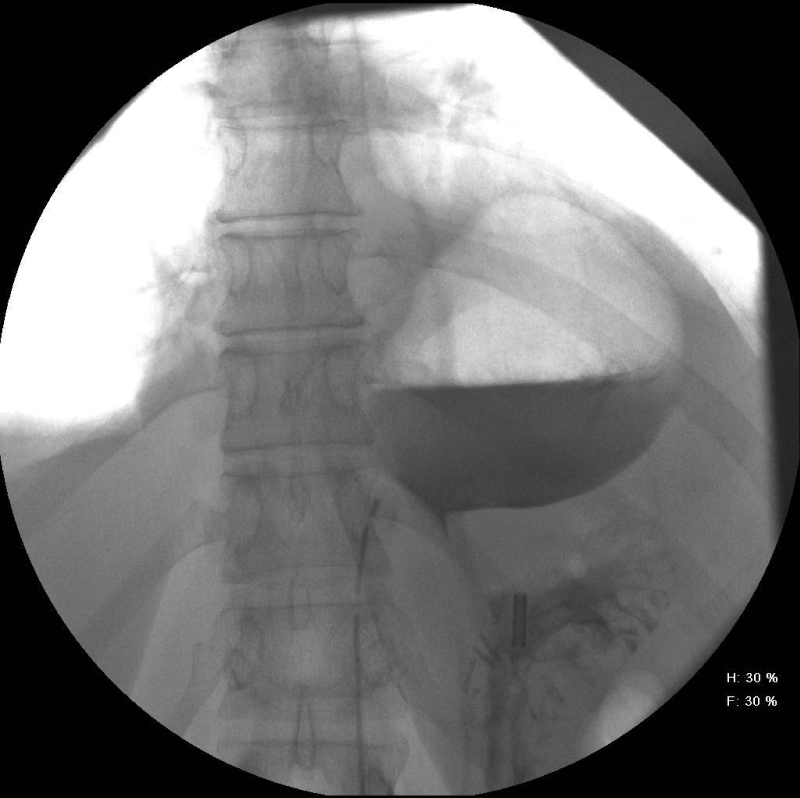

She initially had a Chest X-Ray, which showed a 5 cm, round and well-defined shadow behind the heart suspected to be of HH. This was followed by an enhanced Computed Tomography (CT) Thorax (Figure 1) that showed the CXR abnormality corresponded to a possible 6 cm sequestered lung segment. After discussion in the respiratory Multidisciplinary Team (MDT) meeting she was investigated further with a bronchoscopy. However, the bronchoscopy was normal and bronchial washings did not show any malignant cells. A positron emission tomography computed tomography (PET/CT) was then performed and showed a 6.5 cm thick-walled air filled mass in the lower lobe of the left lung with intense peripheral Fluoro Deoxy Glucose (FDG) uptake suspicious of a malignancy. A barium swallow showed the lesion seen on CT to be continuous with the lumen of the oesophagus (Figure 2). Following this, a large HH at 25 cm was visualised on an Oesophago Gastroduo Denoscopy (OGD) examination.